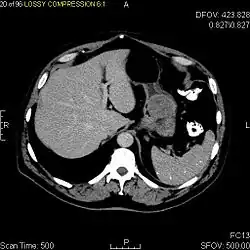

КТ-скан ГИСО в кардии желудка. Новообразование субмукозной локализации, гиперваскулярное, распространяется в просвет органа. При эндоскопии по поводу желудочно-кишечного кровотечения были обнаружены изъязвлённые массы.

Так как ГИСО происходят из мышечного слоя (который располагается глубже слизистого и подслизистого слоёв), небольшие ГИСО чаще визуализируются как подслизистое или внутристеночное объёмное образование. При исследовании желудочно-кишечного тракта с барием обычно выявляются ровные контуры образования, формирующие прямой или тупой угол со стенкой, что наблюдается и при любых других интрамуральных процессах. Поверхность слизистой интактна, за исключением случаев изъязвления, которые присутствуют при 50 % ГИСО. При КТ с контрастным усилением, небольшие ГИСО обычно визуализируются как интрамуральные образования с ровными, чёткими контурами и гомогенным контрастированием.

По мере роста опухоли, она может проецироваться снаружи от органа (экзофитный рост) и/или в просвете органа (интралюминальный рост); чаще всего ГИСО растут экзофитно, таким образом большая часть опухоли располагается в проекции брюшной полости. Если увеличение объёма опухоли опережает рост её кровоснабжения, опухоль может некротизироваться в толще, с формированием центральной зоны жидкостной плотности и кавитацией, что может приводить к изъязвлению и формированию соустья с полостью органа. В этом случае исследование с бариевой взвесью может демонстрировать газ, уровни газ/жидкость или депонирование контрастного препарата в этих областях.[17][18] При КТ с контрастным усилением крупные ГИСО выглядят негомогенно, в связи с неоднородностью структуры опухоли, обусловленной участками некроза, кровоизлияниями и полостями, что радиологически проявляется контрастированием опухоли преимущественно по периферии.[16]

Злокачественность может проявляться локальной инвазией и метастазами, обычно в печень, сальник и брюшину. Однако встречаются случаи метастазирования в кости, плевру, лёгкие и забрюшинное пространство. По сравнению с аденокарциномой желудка или лимфомой желудка/тонкой кишки, злокачественная лимфаденопатия при ГИСО не типична (<10 %).[16] При отсутствии метастазов радиологическими признаками злокачественности являются большие размеры опухоли (>5 cm), гетерогенное контрастирование после введения контрастного препарата и наличие изъязвлений.[3][16][22] Также явно злокачественное поведение (без учёта опухолей со злокачественным потенциалом) реже наблюдается при ГИСО желудка, с отношением доброкачественных опухолей к явно злокачественным 3-5:1.[3] Даже в случае наличия радиологических признаков злокачественности, следует учитывать, что они могут быть обусловлены другой опухолью; окончательный диагноз должен быть установлен иммуногистохимическим методом.